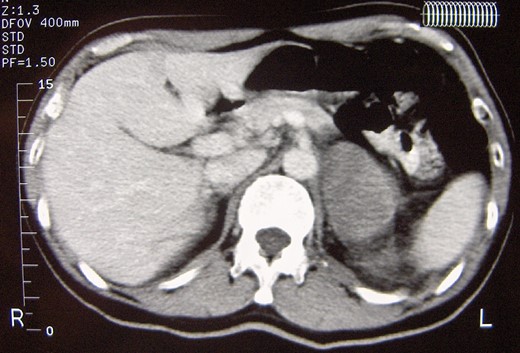

A 52-year-old male with an unremarkable past medical history was referred to our Clinic due to an isolated left adrenal mass and complains of recent onset of proximal muscle weakness. Routine hematologic and biochemical indices were normal. Extensive rheumatologic testing was also normal. Abdominal CT and abdominal MRI revealed an 8 cm left adrenal mass without signs of nearby tissues infiltration or lymph node involvement (Fig. 1), whereas cranial/thoracic CT and thoracic MRI showed no abnormalities. The functional imaging characteristics of the tumor was quite unspecific; in the abdominal CT, the adrenal mass had a density of HU~17 on the unenhanced phase and exhibited a slight gradual enhancement along with a nonspecific delay wash-out pattern both in the abdominal CT and MRI. The endocrine work up was normal: 24-hour urinary catecholamines (8 μg/24 h), metanephrines (258 μg/24 h) and VMA (3.0 μg/) were within normal limits. The 24-hour urinary cortisol level (1.1 mg/dL) and plasma aldosterone to renin ratio (AAR = 1.90) ruled out the possibility of hypercortisolism or primary hyperaldosteronism. The presence of a huge, 8 cm left adrenal mass with inconclusive imaging characteristics and hormonally inactive character deemed the tissue diagnosis mandatory, so a left laparoscopic adrenalectomy was scheduled. The operation was uneventful and the postoperative convalescence was excellent. The patient was discharged in excellent general condition on the third postoperative day.

Abdominal computed tomography showing a well circumscribed 8 cm mass of the left adrenal gland with no signs of local spread or lymph node involvement.